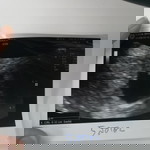

เมื่อวานไปหาหมอมาเนื่องจาก ตกขาวสีน้ำตาล คุณหมอ u/s บอกว่าเห็นน้องไม่ชัด ให้ยากันแท้งมาทาน วันนี้ตอนเข้าห้องน้ำ เจอลิ่มเลืิอดสีน้ำตาล เลยกลับไปหาหมออีกครั้ง คุณหมอถามว่ากี่สัปดาห์แล้ว เราบอก 9w คุณหมอบอกว่าเห็นน้องนะแต่เห็นไม่ชัด ขนาดแค่ 0.7 เท่านั้น เล็กมากสำหรับอายุครรภ์เท่านี้ คุณหมอบอกให้ทำใจเผื่อไว้ กลับมาบ้านเข้าห้องน้ำ เจอลิ่มเลือดสีแดงเข้มอีก ปริมาณมากกว่าเมื่อเช้า ตอนนี้สภาพจิตใจย่ำแย่มากค่ะ ทำใจไม่ได้เลย กลัวน้องจะไม่อยู่กับเราแล้ว ?